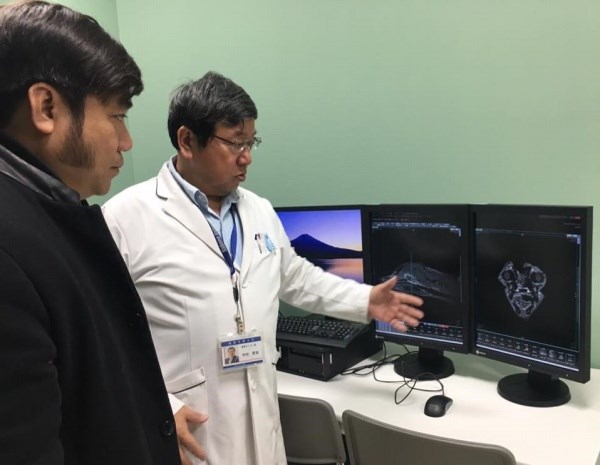

| Khoa Thú y tham gia đào tạo ngắn hạn về phẫu thuật khối u hộp sọ của chó tại Nhật Bản (02/02/2017) |